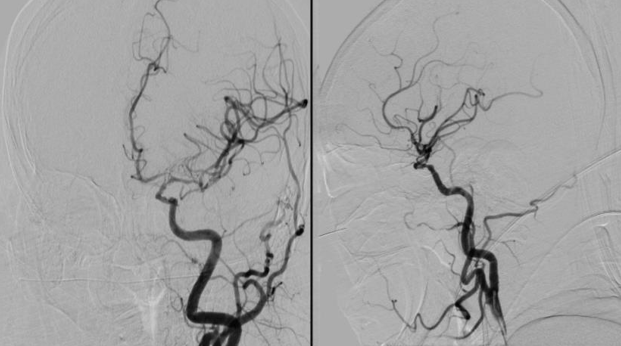

治疗过程

将 6F 导引导管送至 C3 段。

导丝怎么扩【载药时代 球扩天下】NOVA DES®颅内药物洗脱支架在颈内动脉颅内段重度狭窄中的应用体会二例!_https://www.jmylbn.com_新闻资讯_第24张

导引导管到位,导丝通过病变